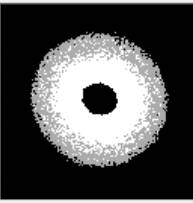

покладено аналіз дифракційних картин мазків крові, які були отримані при

проходженні лазерного випромінювання довжиною хвилі 635 нм (рис.1).

а) б)

Рис.1. ДК венозної крові: а) здорової людини; б) з патологіями.